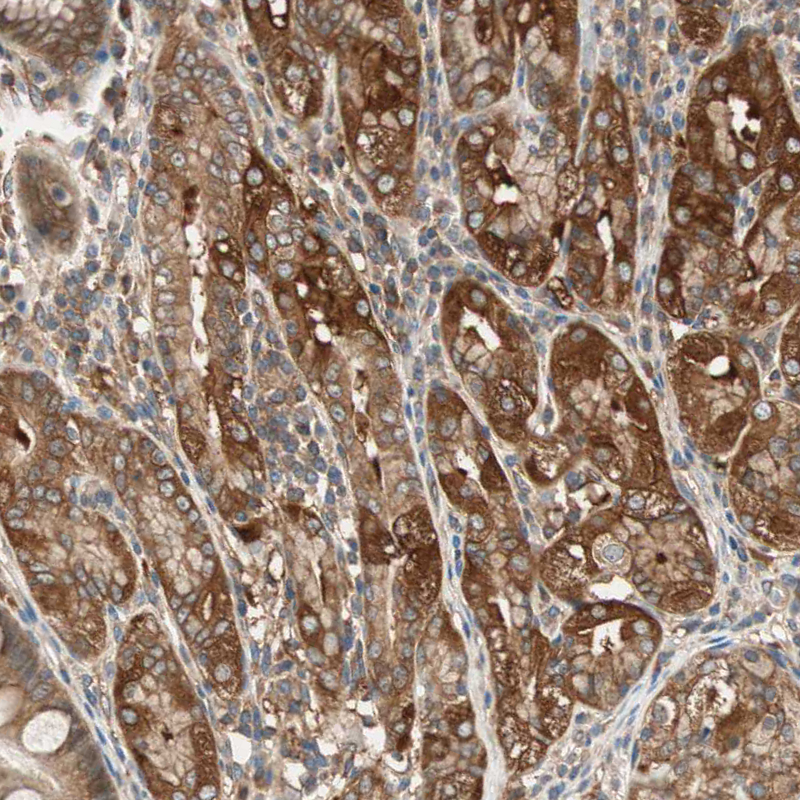

Immunohistochemistry analysis in human cerebral cortex and skeletal muscle tissues using HPA005750 antibody. Corresponding WASL RNA-seq data are presented for the same tissues.